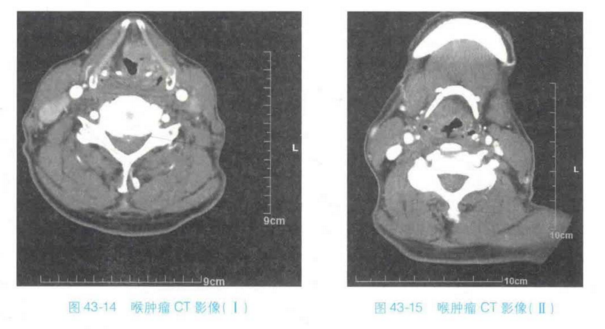

临床多使用轴位扫描,现使用螺旋CT,可以通过后处理技术完成喉的多平面重建三维重建,以及仿真内镜技术。冠状位影像可以显示杓会厌皱裂、室带、喉室、声带、声门旁间隙等结构的关系。通过CT检查可为临床提供充分的信息,包括外伤性疾病组织受损的情况,肿瘤性疾病的病变范围等情况(如图所示),个别情况需配合MRI检查(图43-14、图43-15)